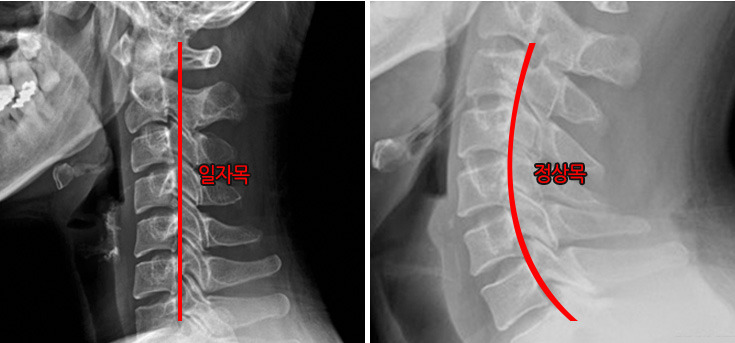

일자목 증후군이라고도 하는 거북목 증후군의 원인은 바르지 못한 자세와 잘못된 생활습관을 들 수 있습니다. 장시간 고개를 숙이고 있거나 스마트폰을 오래 들여다보는 습관이 거북목을 유발하는데요, 이로 인해 목뼈의 모양이 변형된 것입니다.

건강한 목뼈는 옆에서 보았을 때 C자 형태로 척추의 정상적인 커브를 나타내야 하는데, 거북목 증후군을 겪는 환자의 목뼈는 일자로 뻗어 있거나 역C자 모양으로 변형되어 있습니다. 이러한 변형은 목의 충격 완화 능력을 떨어뜨려 외부 충격이 척추에 그대로 전달되면서 디스크 퇴행을 촉발하게 됩니다.